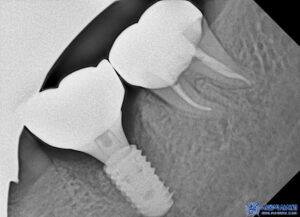

이후 임플란트의 치유기간을 거치고

뼈와의 결합이 안정적으로

이루어진 것을 확인 후

뒤 치아와 함께 보철 작업을

시작하였습니다.

본원 원내기공소에서 상주하는

10년 차 이상의 전문 치과기공실장님이

정교하게 제작한 개인맞춤형

보철물을 세팅해 드렸습니다.

보철물을 외주를 주지 않고,

직접 모두 제작하고 있기에

제작 기간도 단축되고,

환자분의 구강상태에 맞춤형으로

정밀하게 디자인 또한 가능합니다.